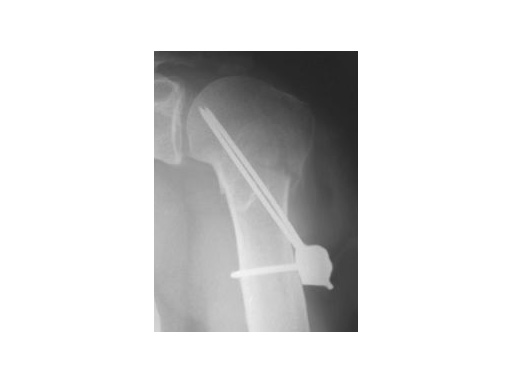

62 year old female patient

Fig 2

postoperative

Fig 3

Fracture healed